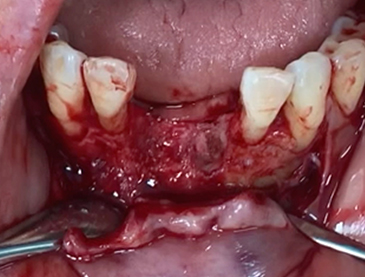

A clinical case using resorbable membrane

• A clinical case using resorbable membrane 2